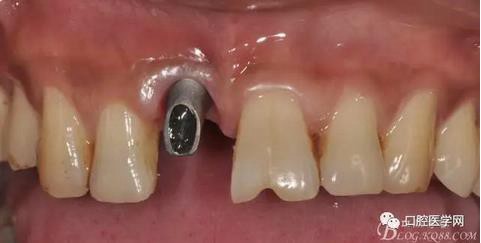

圖19 口內(nèi)修復(fù)基臺(tái)正位照

圖20 口內(nèi)修復(fù)基臺(tái)正位照